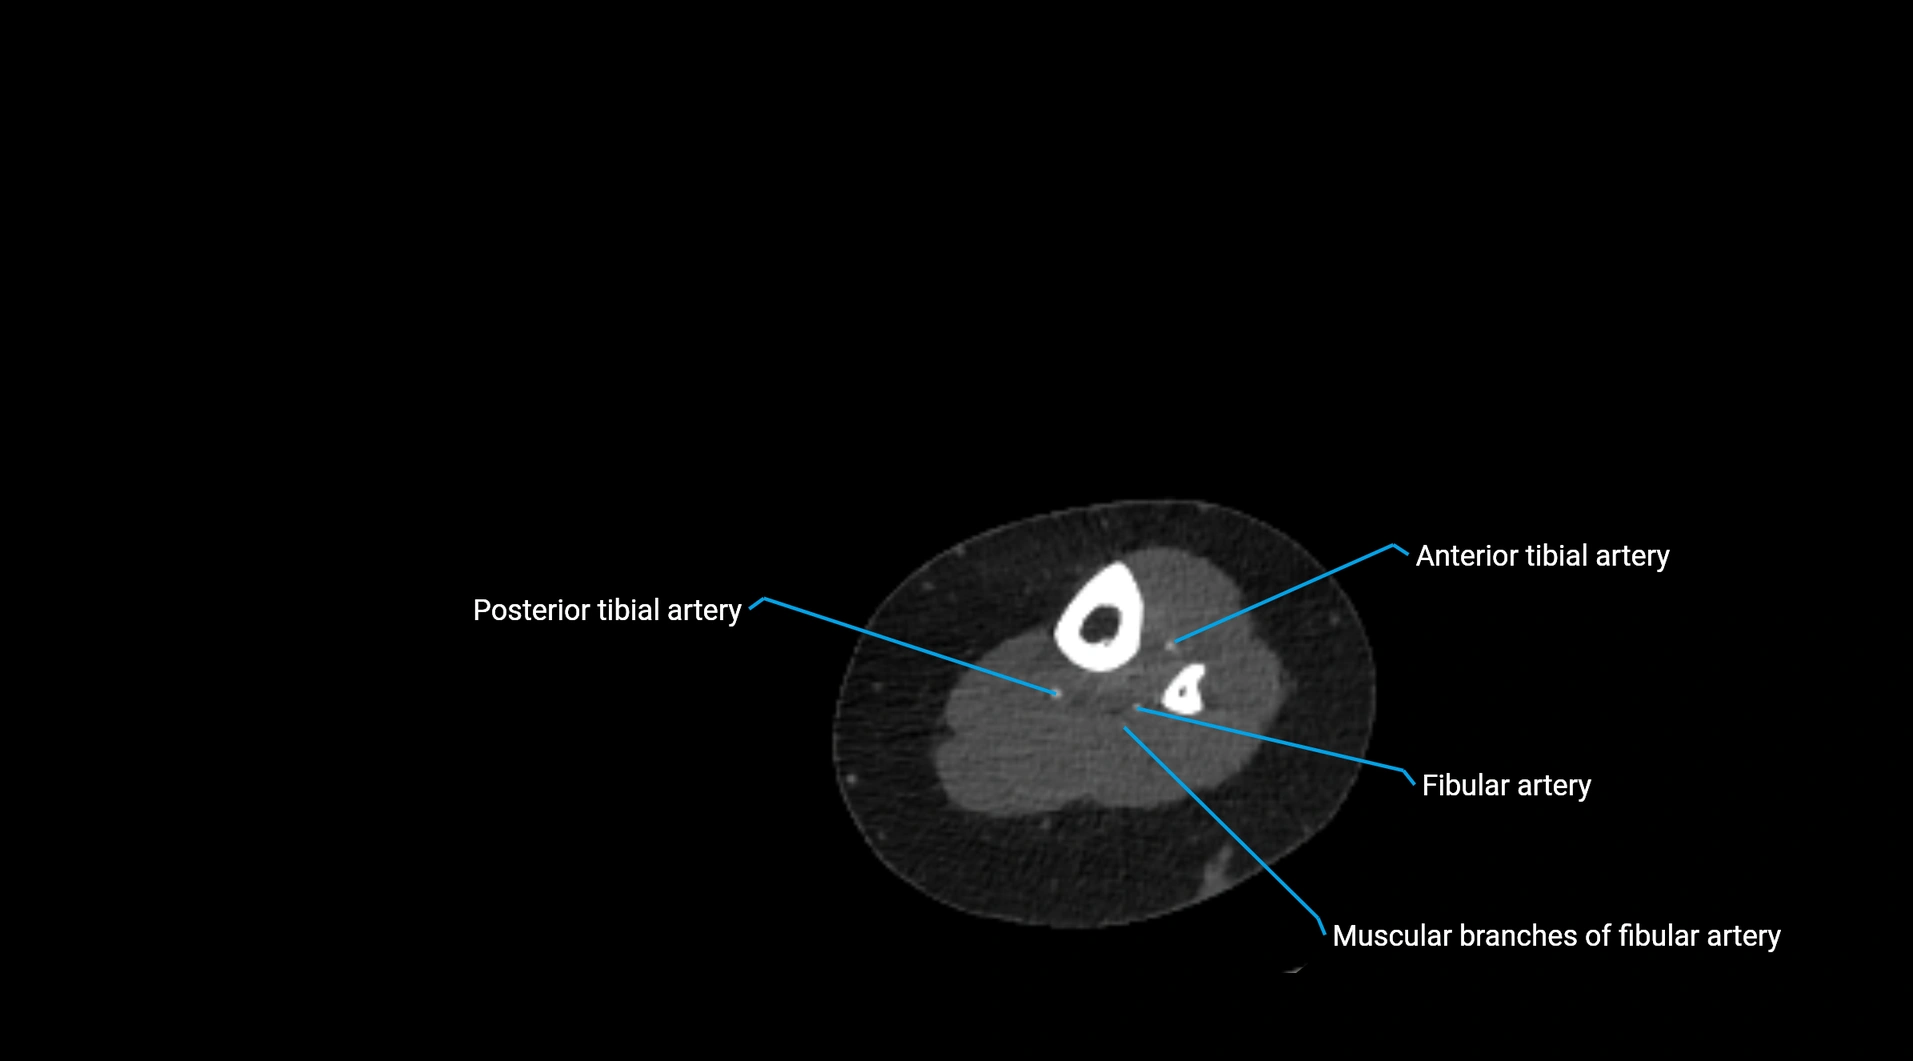

CT images

image

Contrast-enhanced CT (CTA):

• Gold standard for abdominal aortic imaging

• Provides excellent detail of lumen, wall, aneurysm, thrombus, and branch vessels

• Multiplanar and 3D reconstructions help in aneurysm measurement, stent graft planning, and dissection evaluation